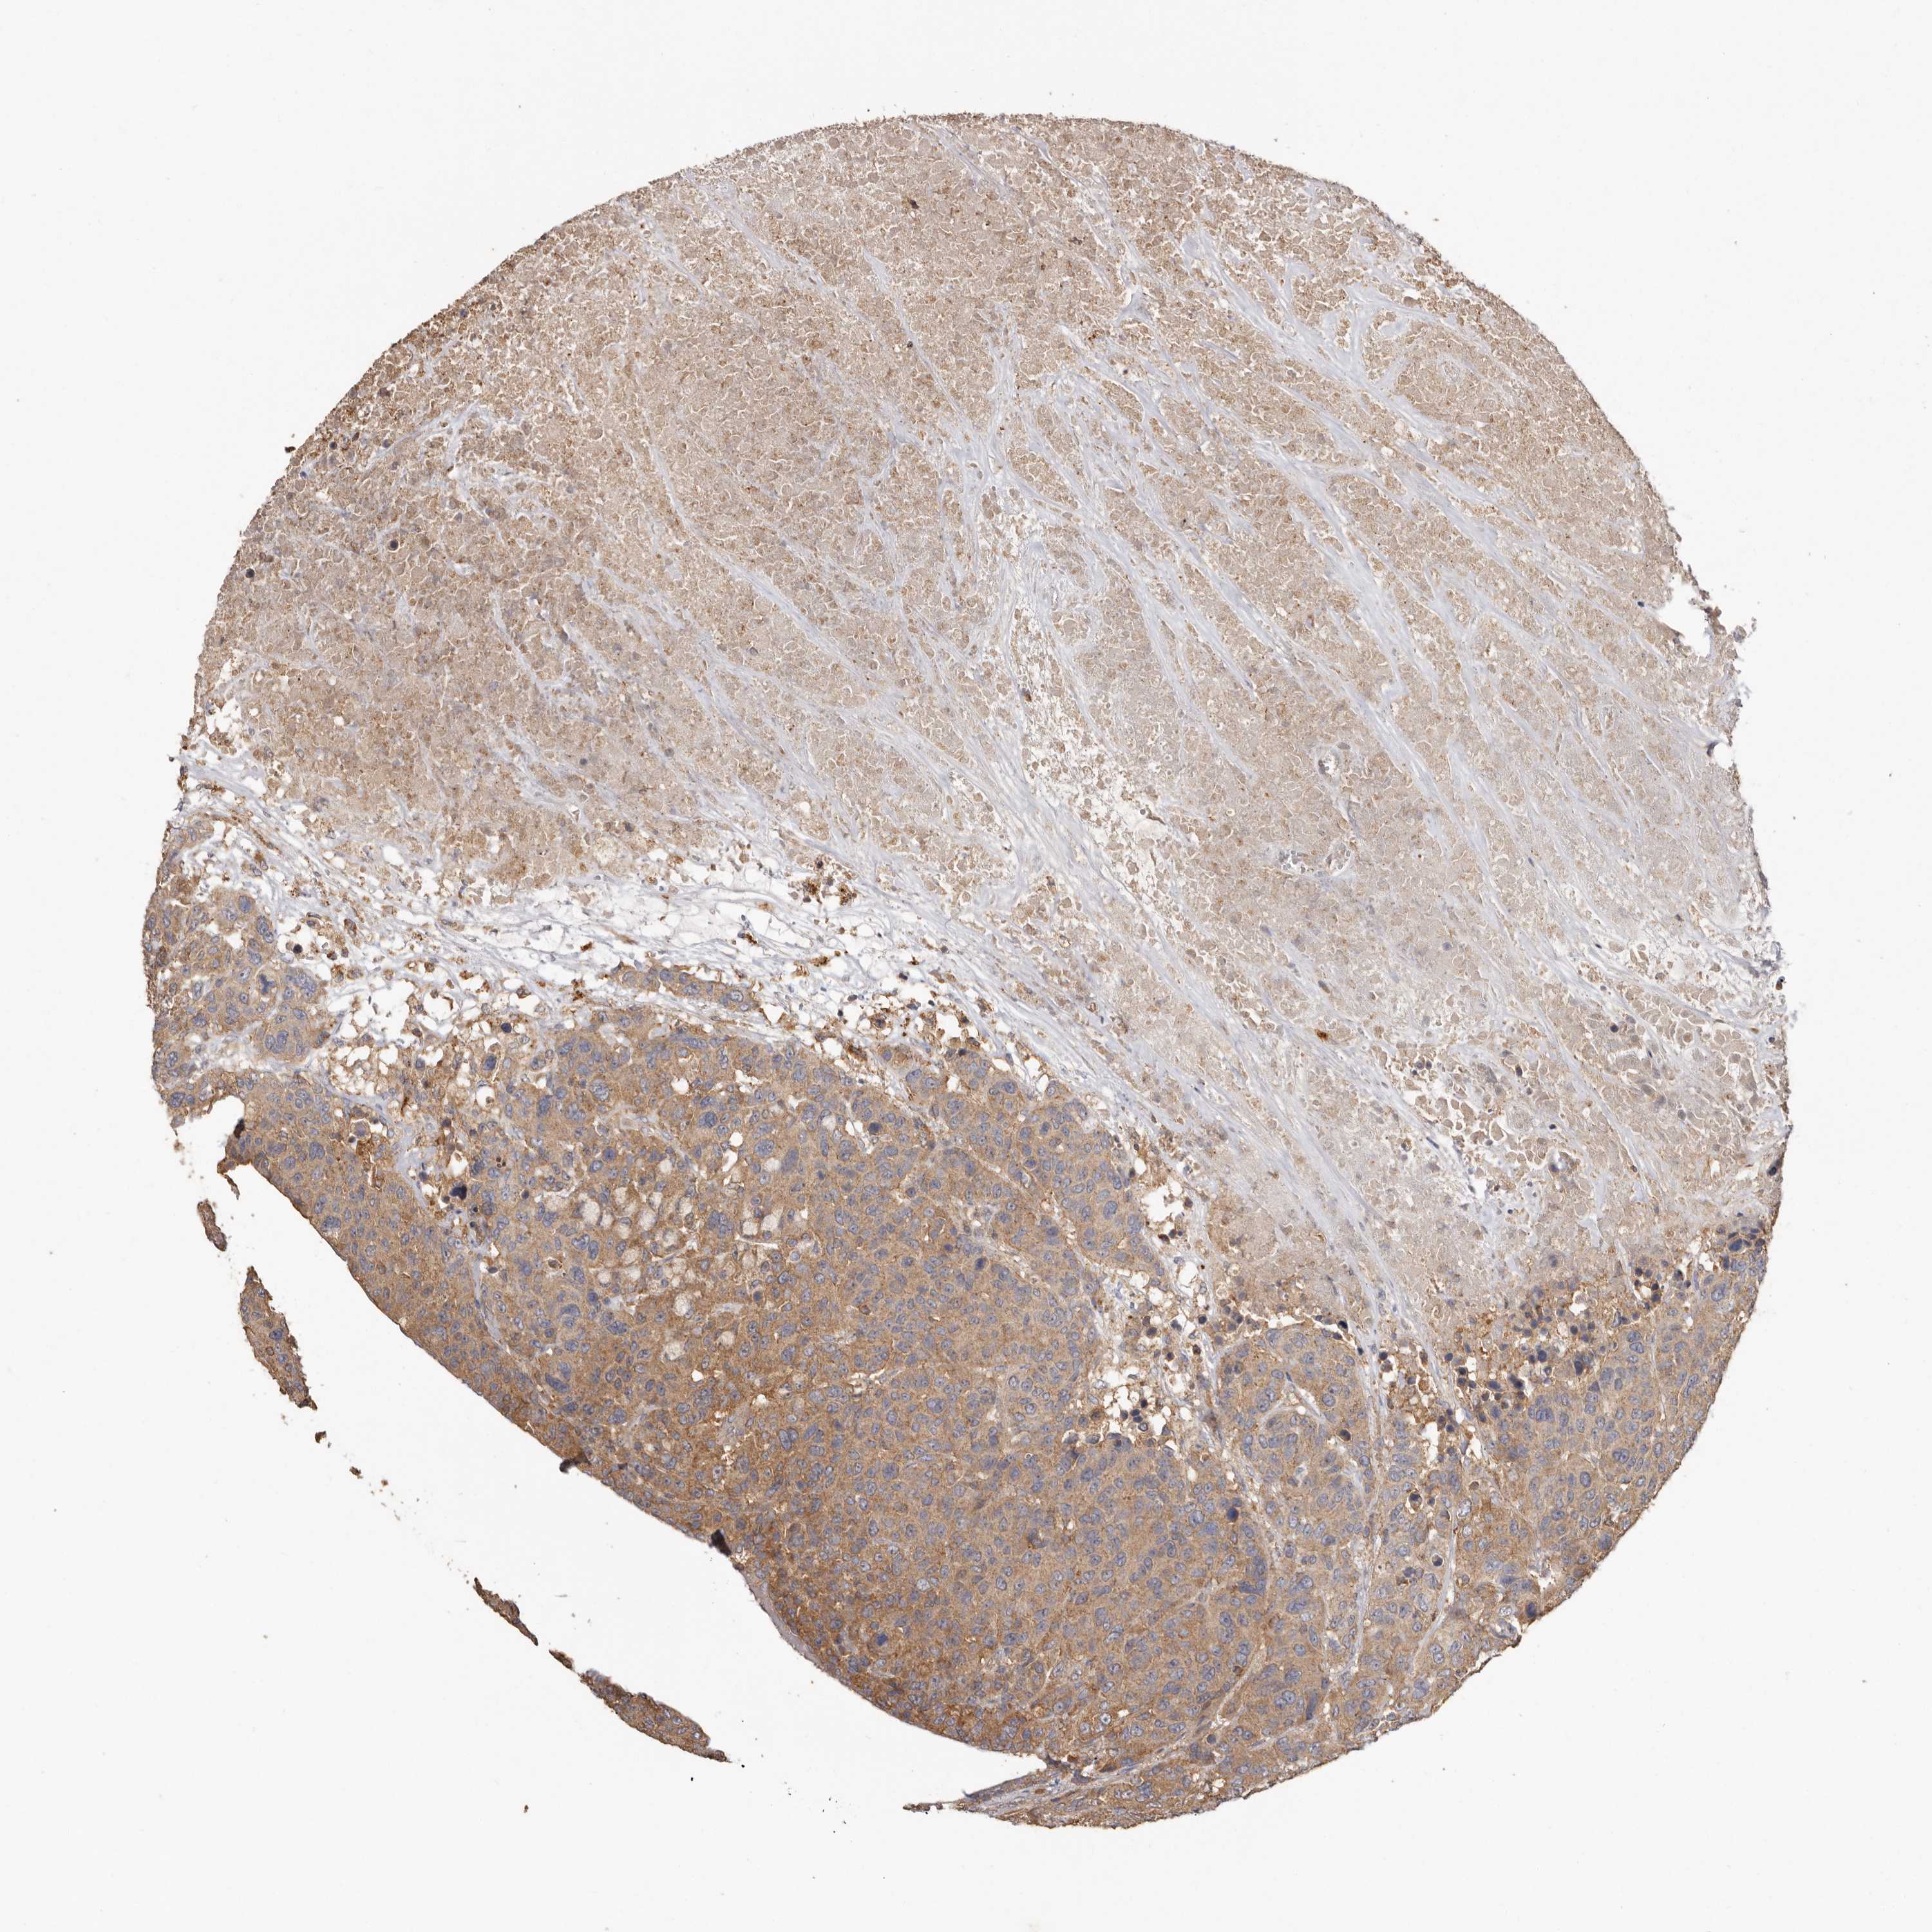

CANCER BREAST CANCER Show tissue menu

BRCA TCGA BRCA VALIDATION PROTEIN EXPRESSION